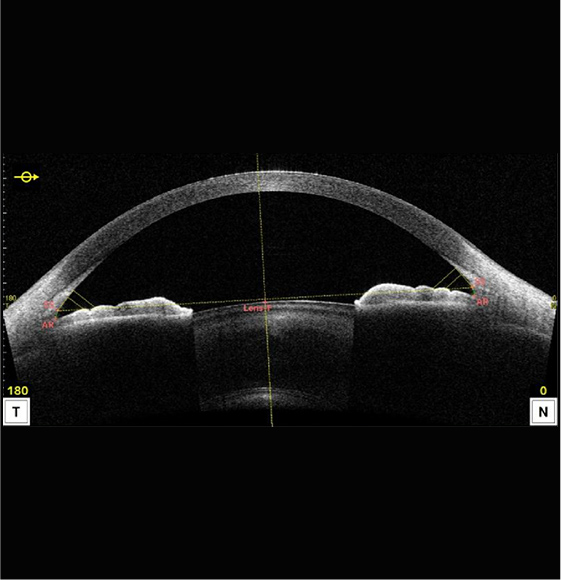

前眼部光干渉断層計(前眼部OCT)

角膜・虹彩・水晶体など前眼部の断層画像を撮影し、隅角(眼の水の流れ道)の状態や角膜形状などから、緑内障や角膜疾患を早期発見